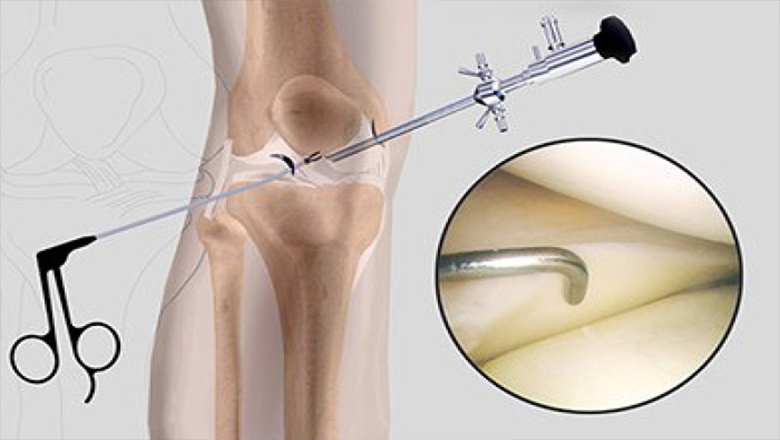

Arthroscopic (Keyhole) Surgery

We use advanced arthroscopy techniques to perform minimally invasive procedures, which usually means smaller cuts, less pain, and a quicker recovery for patients.

Procedures:

- ACL & PCL reconstruction

- Meniscus repair / meniscectomy